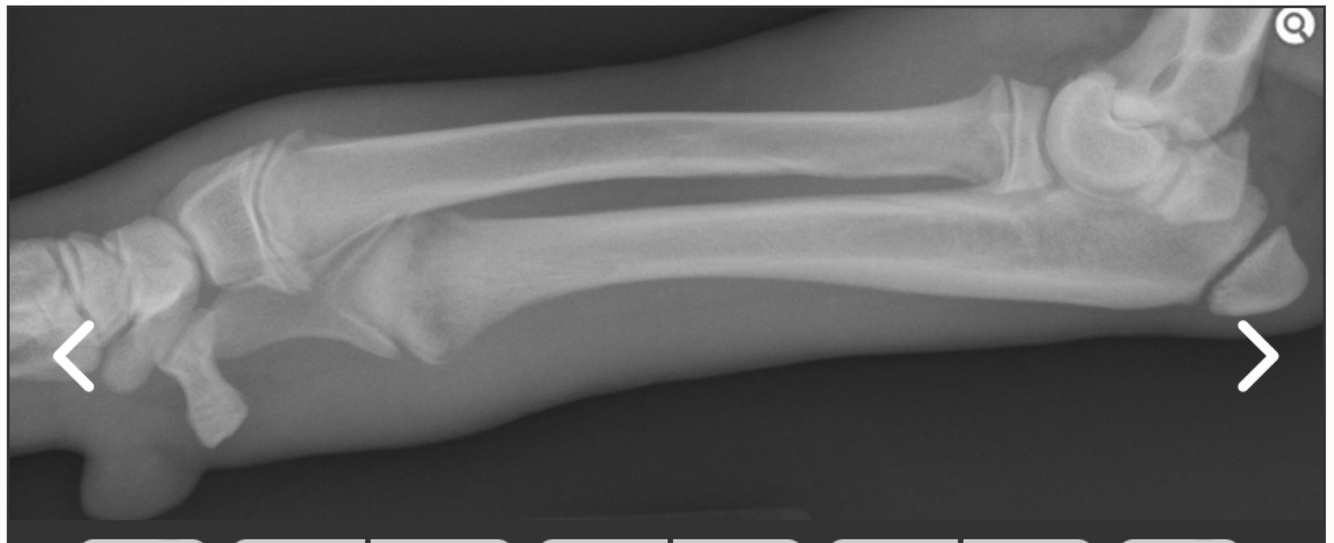

A 4-month old male intact Great Dane presents for lethargy and reluctance to stand. He is non-weight bearing on his left forelimb. You localize pain and swelling to the distal radius and ulna and take the following radiograph. What do you tell the owner about recovery and prognosis?

• Prognosis is usually good but angular limb deformity is a possible complication. Recovery relies on supportive care and can take days to weeks. Most dogs with this disease will have 1 or 2 episodes and recover.

Answer: Prognosis is usually good but angular limb deformity is a possible complication. Recovery relies on supportive care and can take days to weeks. Most dogs with this disease will have 1 or 2 episodes and recover.

Explanation

Hypertrophic osteodystrophy (HOD) is a disease of large, rapidly growing dogs. The distal metaphyses of the forelimbs are more commonly affected and can be swollen. Radiographic findings include metaphyseal flaring and the classic “double physeal line.” Treatment is supportive with anti-inflammatories or steroids, pain medications, and activity restriction.

Septic arthritis can cause lameness, joint pain and swelling. Radiographs can show bone destruction and osteolysis with chronic disease as well as irregularities in the joint space. Osteosarcoma causes bony lysis and proliferation at the metaphyseal region of long bones. These are commonly in the distal radius/ulna, proximal humerus, proximal tibia, and distal femur (“away from the elbow and towards the knee”). Age does not rule out this disease as it has been diagnosed in animals as young as 6 months.